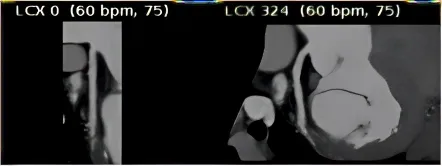

人工智能图像

我立刻换到另一台需要人工后处理的设备,重新手动重建血管。

人工处理图像

结论明确:左回旋支中段,完全闭塞。